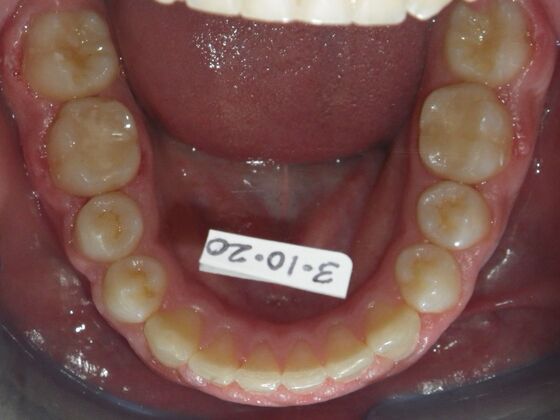

Orthodontic treatment in Phases: Case 8

Dylan presented with a functional crossbite in which we used removable expansion appliances for 12 months, followed by bracketing of upper and lower teeth including primary ones to gain alittle more expansion, allowed to wear retainers for 6 months and then followed closely with 6 month ortho recalls and began Phase 2 treatment within 24 months and finished his ortho treatment.